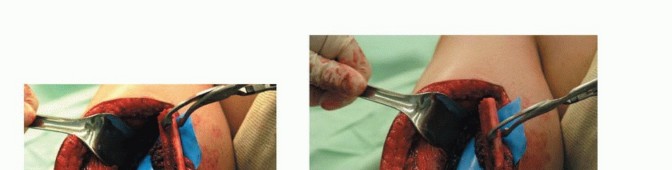

- وضع المريض وشق الجراحة: لعلاج عيب في الطرف السفلي، يُوضع المريض على ظهره مع فصل الفخذين. تُثنى ورك وركبة الطرف المانح (TECH FIG 1). يتموضع الفريق الأول، المسؤول عن استئصال الورم (الفريق الأزرق)، على طول الجانب الإنسي أو الوحشي للطرف المستقبل. يتموضع الفريق الثاني (الفريق الأحمر)، المسؤول عن حصاد طعم الشظية من الطرف المانح، على طول جانبه الوحشي.

وضع المريض

يُوضع المريض على ظهره على طاولة العمليات مع فصل الفخذين وثني ورك وركبة الطرف المانح. يتموضع الفريق المسؤول عن استئصال الورم (باللون الأزرق) على طول الجانب الإنسي أو الوحشي للطرف المستقبل، حسب الحاجة. يتموضع الفريق المسؤول عن إزالة طعم الشظية من الطرف المانح (باللون الأحمر) على طول جانبه الوحشي.